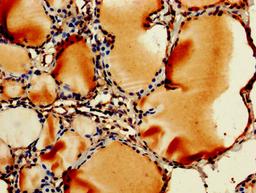

IHC image of CSB-PA00065A0Rb diluted at 1:250 and staining in paraffin-embedded human thyroid tissue performed on a Leica BondTM system. After dewaxing and hydration, antigen retrieval was mediated by high pressure in a citrate buffer (pH 6.0). Section was blocked with 10% normal goat serum 30min at RT. Then primary antibody (1% BSA) was incubated at 4°C overnight. The primary is detected by a biotinylated secondary antibody and visualized using an HRP conjugated SP system.